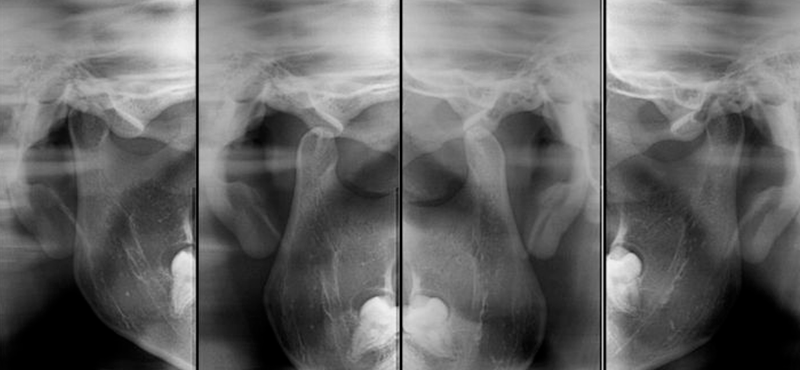

ATM - 4 Posições Digital

Avalia-se o deslocamento dos côndilos, assimetria dos côndilos, fraturas e anomalias condilares.